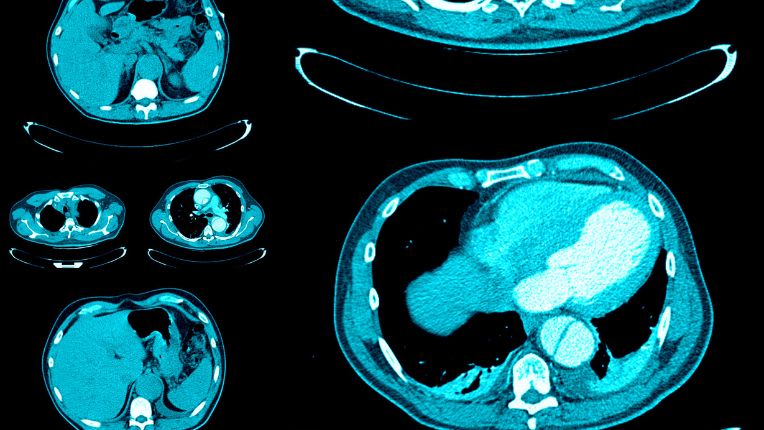

Le scanner thoracique, ou scanner du thorax, désigne un examen d’imagerie médicale destiné à explorer la cage thoracique. Grâce à l’émission de rayons X, le scanner thoracique permet de visualiser sur un écran d’ordinateur des images en coupe d’une grande précision. Le médecin peut alors observer l’état des poumons, de la plèvre, du cœur, des vaisseaux sanguins (artère pulmonaire, artères coronaires), des vaisseaux lymphatiques ou encore de la glande thyroïde et des os (sternum, côtes). La prescription d’un scanner du thorax peut répondre à divers objectifs médicaux. Elle est effectuée seule ou en complément d’autres examens.